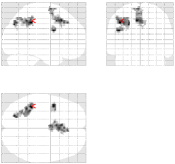

For the aC-aS contrast, Fig. 9 [top] shows, for the most significant slice and , that all pMRI reconstruction algorithms succeed in finding evoked activity in the left parietal and frontal cortices, more precisely in the inferior parietal lobule and middle frontal gyrus according to the AAL template666available in the xjView toolbox of SPM5.. Tab. 3 also confirms a bilateral activity pattern in parietal regions for . Moreover, for , Fig. 9 [bottom] illustrates that our pipeline (UWR-SENSE and 4D-UWR-SENSE) and especially the proposed 4D-UWR-SENSE scheme enables to retrieve reliable frontal activity elicited by mental calculation, which is lost by the the mSENSE algorithm. From a quantitative viewpoint, the proposed 4D-UWR-SENSE algorithm finds larger clusters whose local maxima are more significant than the ones obtained using mSENSE and UWR-SENSE, as reported in Tab. 3. Concerning the most significant cluster for , the peak positions remain stable whatever the reconstruction algorithm. However, examining their significance level, one can first measure the benefits of wavelet-based regularization when comparing UWR-SENSE with mSENSE results and then additional positive effects of temporal regularization and 3D wavelet decomposition when looking at the 4D-UWR-SENSE results. These benefits are also demonstrated for .

| mSENSE | UWR-SENSE | 4D-UWR-SENSE | |

|---|---|---|---|

|

|

|

|

|

|

|

| cluster-level | voxel-level | |||||

| p-value | Size | p-value | T-score | Position | ||

| mSENSE | 320 | 6.40 | -32 -76 45 | |||

| 163 | 5.96 | -4 -70 54 | ||||

| 121 | 6.34 | 34 -74 39 | ||||

| 94 | 6.83 | -38 4 24 | ||||

| UWR-SENSE | 407 | 6.59 | -32 -76 45 | |||

| 164 | 5.69 | -6 -70 54 | ||||

| 159 | 5.84 | 32 -70 39 | ||||

| 155 | 6.87 | -44 4 24 | ||||

| 4D-UWR-SENSE | 454 | 6.54 | -32 -76 45 | |||

| 199 | 5.43 | -6 26 21 | ||||

| 183 | 5.89 | 32 -70 39 | ||||

| 170 | 6.90 | -44 4 24 | ||||

| mSENSE | 58 | 0.028 | 5.16 | -30 -72 48 | ||

| UWR-SENSE | 94 | 0.003 | 5.91 | -32 -70 48 | ||

| 60 | 0.044 | 4.42 | -6 -72 54 | |||

| 4D-UWR-SENSE | 152 | 6.36 | -32 -70 48 | |||

| 36 | 0.009 | 5.01 | -4 -78 48 | |||

| 29 | 0.004 | 5.30 | -34 6 27 | |||

Fig. 10 illustrates another property of the proposed pMRI pipeline, i.e. its robustness to the between-subject variability. Indeed, when comparing subject-level Student’s -maps reconstructed using the different pipelines (), it can be observed that the mSENSE algorithm fails to detect any activation cluster in the expected regions for the second subject (see Fig. 10 [bottom]). By contrast, our 4D-UWR-SENSE method retrieves more coherent activity while not exactly at the same position as for the first subject.

| mSENSE | UWR-SENSE | 4D-UWR-SENSE | |

|---|---|---|---|

| Subj. 1 |  |

|

|

| Subj. 2 |  |

|

|